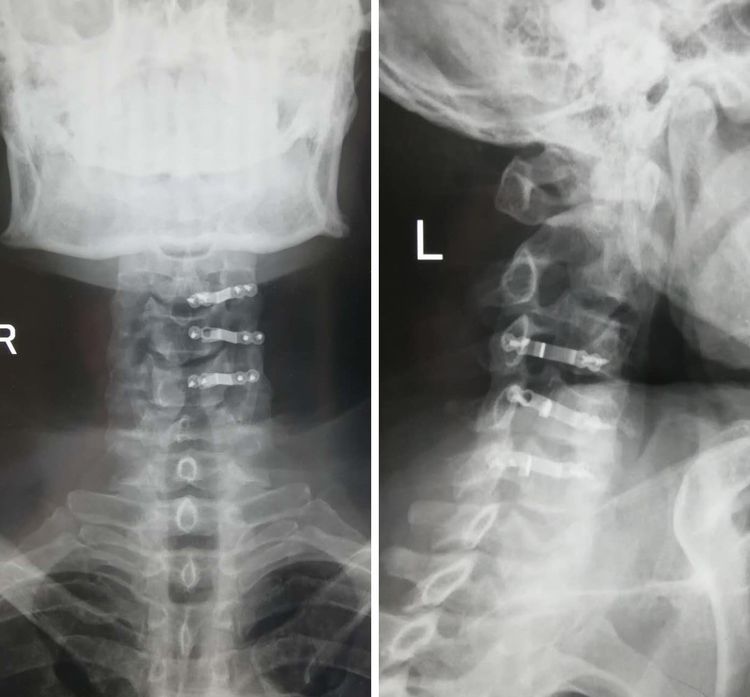

检查明确患者系左侧血气胸,颈髓损伤,无椎体骨折等表现。患者生命体征平稳,在第一时间完成头皮裂伤清创缝合后,结合患者体征及影像学检查,考虑患者发育性颈椎管狭窄,受伤机制系头部外伤至颈椎过伸,引发颈髓急性损伤。在明确受伤机制及损伤颈髓节段,拟定了颈椎管扩大成形手术治疗方案。颈椎手术需全身麻醉,由于患者左侧血气胸,为防止麻醉过程中出现张力性气胸。骨科与胸外科、麻醉科讨论后制定了,在不增加患者创伤的前提下,依旧采用静脉全麻,胸外科备诊防止张力性气胸等危机情况。针对该患者骨科改进了椎管扩大成形术操作,保留了患者棘间韧带、棘上韧带,有效减少了手术时间及术中出血。